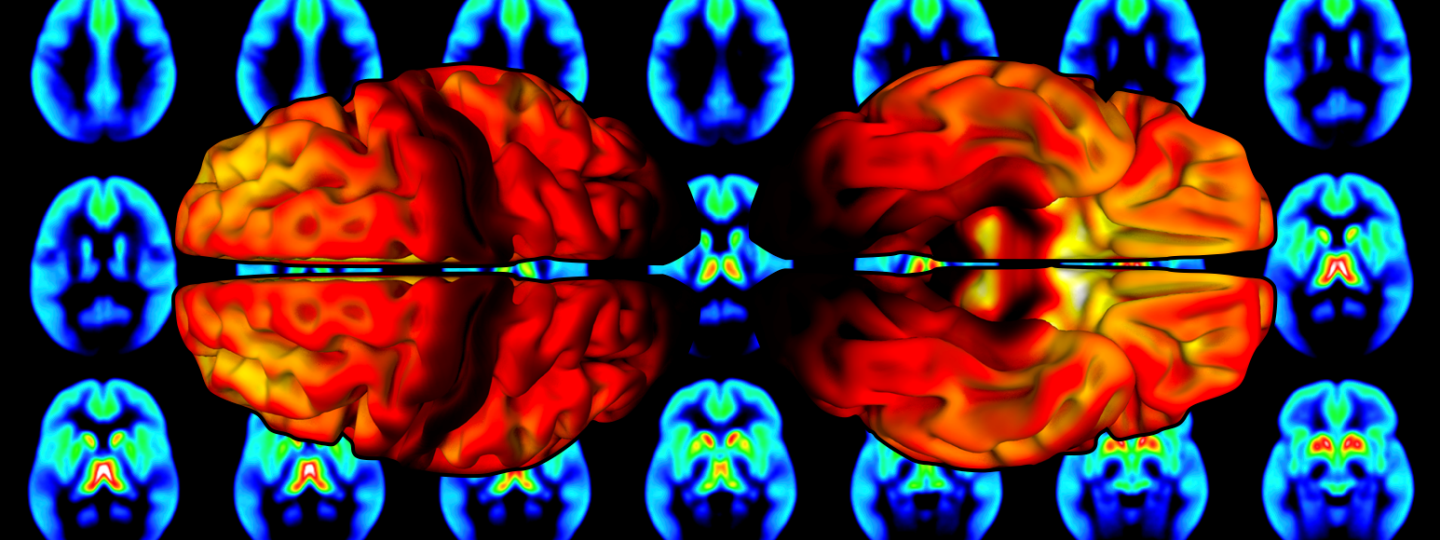

Brain’s μ-opioid receptors act as important mediators for body’s own opioids in the brain. This study analysed positron emission tomography (PET) brain scans targeting μ-opioid receptors from 204 individuals with no neurologic or psychiatric disorders. This database was compiled with new computational tools developed at the Turku PET Centre.

Image: Distribution of μ-opioid receptors in the human brain. Warmer colour stands for more receptors, and colder colour for less receptors. The original image has been published in the NeuroImage.